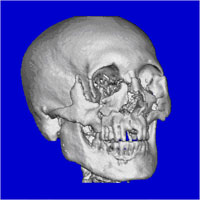

头颅3维CT扫描 可以了解复杂的解剖关系,而且可以用所得到的数据进行个性化修复体的制作。

图7 三维重建CT

(图片来自于病案收藏)